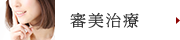

写真では青で囲った部分が虫歯で歯を保存するのが

難しく抜歯となりました。

抜歯を行うと赤いラインの部分が上顎洞という空洞に

なり、インプラントを差し込む骨がないため

ソケットプリザベーションを行いました。